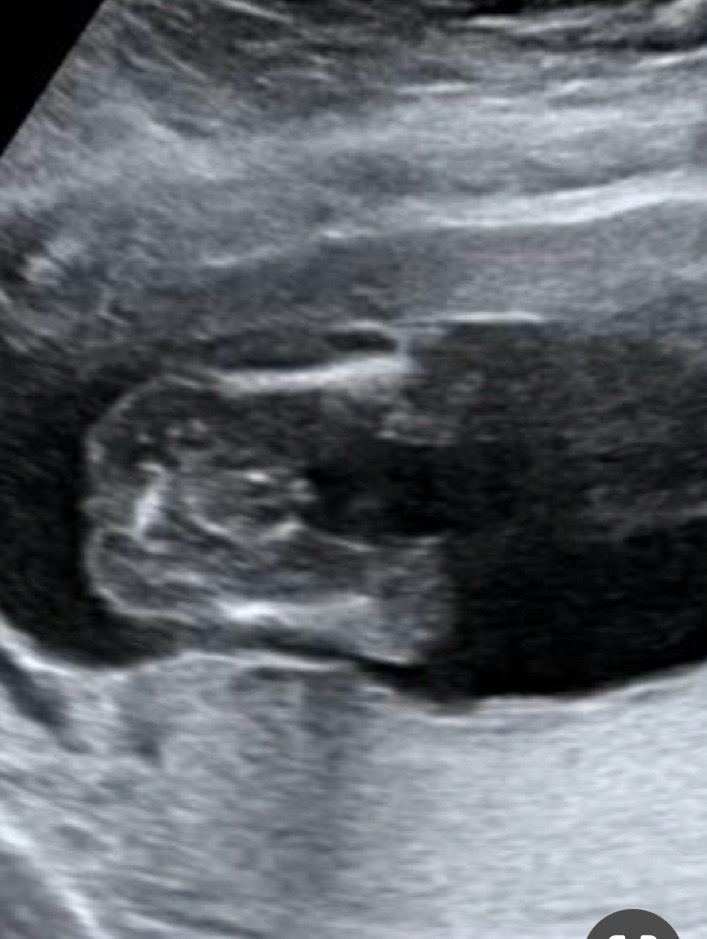

아들일까요 딸 일까요??

의사샘은 아들이라는데…..제눈엔 도대체 모르겠어요 ㅠㅠ

아들 맞는것 같아요ㅎㅎ

아들인거같아요! 저는 딸인데 아무것도 없어요

아들이에요!! 존재감 뿜뿜이네요